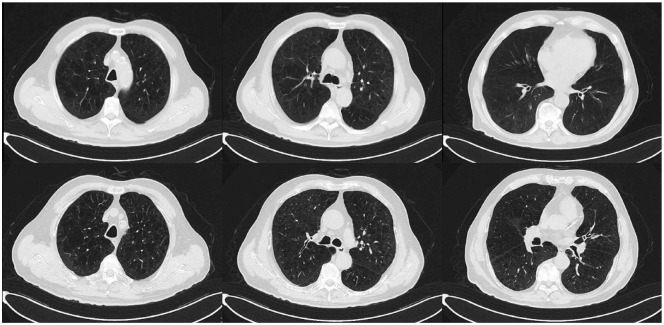

Abstract Image